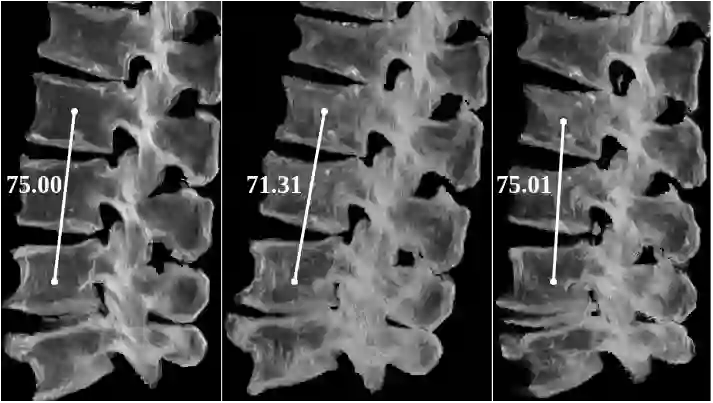

Symptomatic spinal vertebral compression fractures (VCFs) often require osteoplasty treatment. A cement-like material is injected into the bone to stabilize the fracture, restore the vertebral body height and alleviate pain. Leakage is a common complication and may occur due to too much cement being injected. In this work, we propose an automated patient-specific framework that can allow physicians to calculate an upper bound of cement for the injection and estimate the optimal outcome of osteoplasty. The framework uses the patient CT scan and the fractured vertebra label to build a virtual healthy spine using a high-level approach. Firstly, the fractured spine is segmented with a three-step Convolution Neural Network (CNN) architecture. Next, a per-vertebra rigid registration to a healthy spine atlas restores its curvature. Finally, a GAN-based inpainting approach replaces the fractured vertebra with an estimation of its original shape. Based on this outcome, we then estimate the maximum amount of bone cement for injection. We evaluate our framework by comparing the virtual vertebrae volumes of ten patients to their healthy equivalent and report an average error of 3.88$\pm$7.63\%. The presented pipeline offers a first approach to a personalized automatic high-level framework for planning osteoplasty procedures.